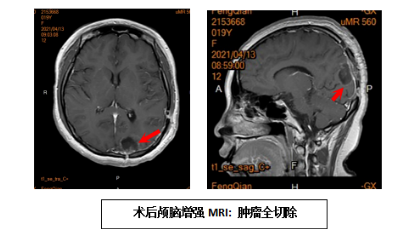

我科与“付继弟颅内感染诊疗团队”进行了密切合作,成立了“中枢神经系统感染诊治中心”,已经成功开展了各种原因引起的颅内、椎管内顽固性严重感染性,和相关神经重症疾病的诊断与治疗,收治的病人来自京外各地医院转来的重症患者。付继弟教授、潘栋超医生亲自参与我科病人的手术及围手术期管理和诊疗工作,经治疗的患者病情均得到有效的转规,好转出院。

我科与首都医科大学附属北京胸科医院建立技术合作,联合“付继弟颅内感染诊疗团队”共同组建了由张立群教授、付继弟教授、张蓬川主任医师、潘栋超和何刚副主任医师组成的“中枢神经系统结核病诊疗团队”,成立了“中枢神经系统结核病诊治中心”,形成了针对“中枢神经系统结核性疾病”的内外科全面系统的诊断及治疗体系,病情均得到有效治疗,病人好转出院。